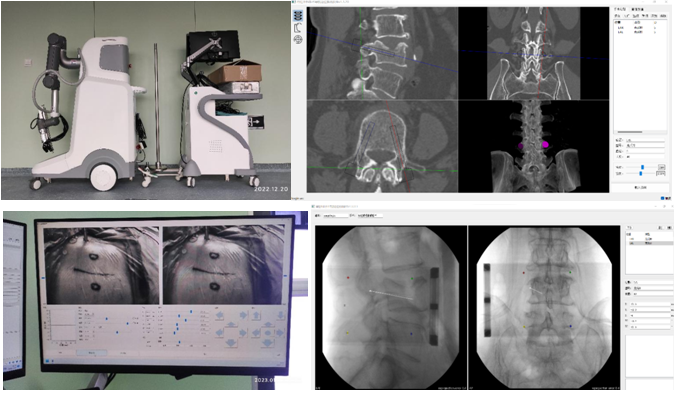

机器人辅助技术是脊柱外科手术向智能化、精准化、微创化发展的又一次飞跃。1月10日,刘时璋主任带领骨科团队精诚合作,在手术室、麻醉科及消毒供应室的鼎力协助下,成功开展三级片

首例机器人辅助局麻下“经皮球囊扩张椎体成形术(PKP)”治疗腰椎压缩性骨折。此例手术较传统的徒手穿刺更为精准、安全、高效,体现了数字医学与骨科智能化的融合发展。

经MRI及CT检查示:腰4椎体压缩性骨折。经专家讨论后,医疗团队拟采用机器人辅助,局麻下行经皮球囊扩张椎体成形术。经过精密的仪器调试和配准,术前进行了反复的模型演练。刘时璋主任团队将患者的CT数据与机器人系统配准,工程师团队将事先规划好的个体化穿刺路径数据植入机器人系统。将术中的正侧位X线透视数据与CT数据融合后,机械臂按照术前规划路径,一次性穿刺成功,位置精准满意。